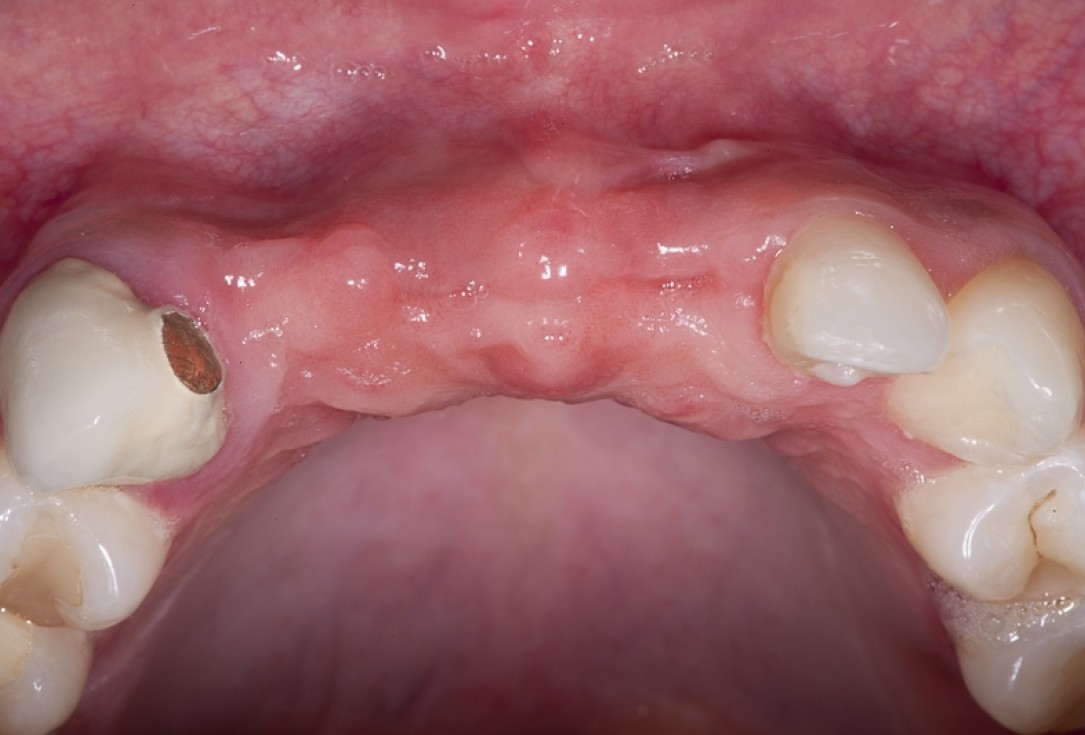

02/17 - Initial situation showing horizontal defect of hard and soft tissue

Block augmentation with maxgraft® block & mucoderm® - Dr. K. Chmielewski